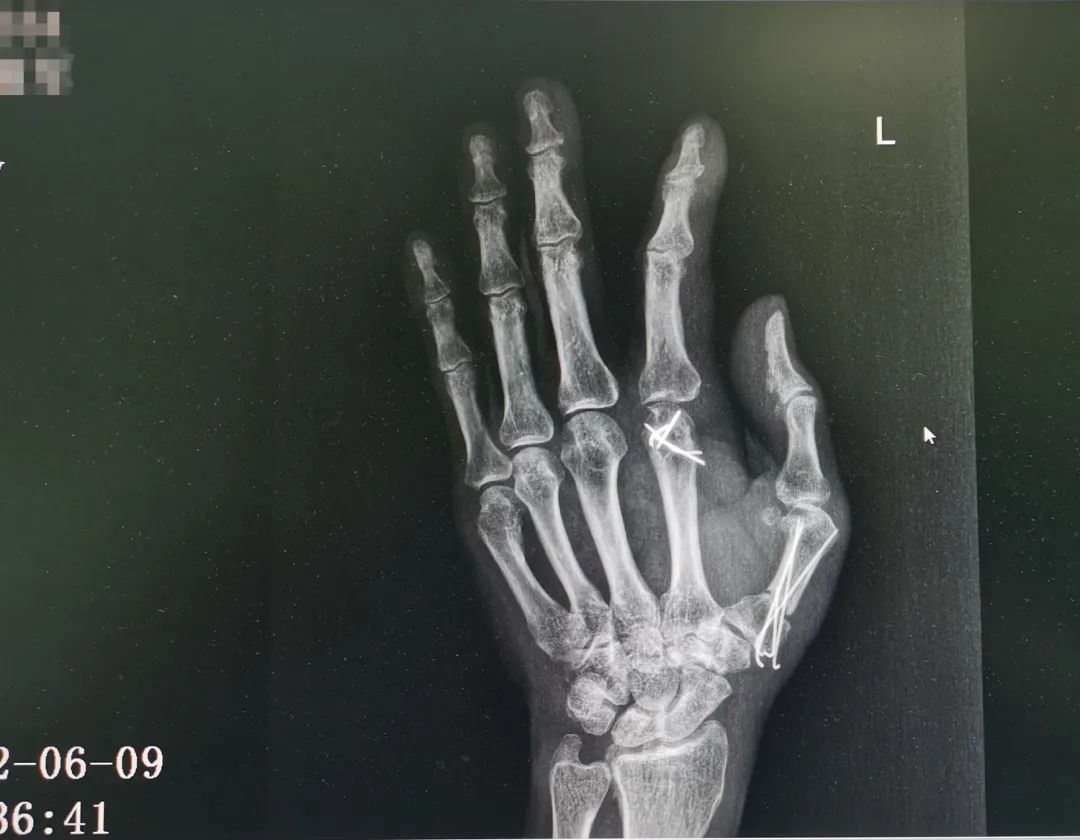

△圖為:患者術(shù)前及術(shù)后復(fù)查X光片對(duì)比

王瑞良主任介紹說(shuō),當(dāng)天晚上,楊大叔是8點(diǎn)左右來(lái)到醫(yī)院,已經(jīng)出現(xiàn)了休克癥狀。醫(yī)生觀察傷口后發(fā)現(xiàn),楊大叔的左手從大魚(yú)際處被割傷,大拇指被完全切斷,只?;⒖谔幧僭S皮膚組織與手掌相連,食指不完全離斷傷,僅近端掌指關(guān)節(jié)尺側(cè)部分軟組織相連。創(chuàng)面內(nèi)污染嚴(yán)重, 離斷血管、神經(jīng)、肌腱、骨頭外露?!皵嗾圃僦策@類(lèi)手術(shù)是跟時(shí)間賽跑的手術(shù),黃金時(shí)間一般為6—8個(gè)小時(shí)。如果超過(guò)時(shí)限,手部神經(jīng)和肌肉就會(huì)壞死,所以我們立即給他進(jìn)行了手術(shù)?!?/span>

積極抗休克治療同時(shí)緊張有序的術(shù)前準(zhǔn)備之后,醫(yī)生仔細(xì)地為楊大叔進(jìn)行清創(chuàng)、骨折復(fù)位固定,耐心地吻合每一根血管、肌腱、神經(jīng),手術(shù)結(jié)束時(shí),已是凌晨。經(jīng)過(guò)三個(gè)半小時(shí)的努力,斷掌再植完成,楊大叔手指血運(yùn)逐漸良好,顏色也變得紅潤(rùn)。

此次復(fù)查,王瑞良主任告訴楊大叔,目前他恢復(fù)情況良好,后續(xù)取出內(nèi)固定釘,并進(jìn)行肌腱松解手術(shù),加上術(shù)后正確的功能康復(fù)鍛煉,大拇指就能重新自由活動(dòng),左手功能達(dá)到基本正常。